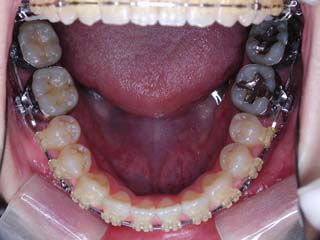

主訴:顎が歪んでいる 下顎が出ている

診断名:骨格性下顎左方偏位を伴う骨格性下顎前突

年齢:28歳

使用した主な装置名:TPB、マルチブラケット装置

抜歯/非抜歯および抜歯部位:抜歯(上顎左右第一小臼歯)

治療期間:動的処置2年3か月、経過観察3年

費用の目安:保険適応 自己負担金として30~50万

リスク、副作用:外科手術によるリスク、マルチブラケット治療に伴う歯根吸収など偶発症が発生するリスクがある。

強い下顎前突と下顎の左方変位がみられます。成長を終了した永久歯列ですので、骨の大きさのズレへのアプローチは大きく別れる所です。程度が小さければ、歯の傾きで補うように解決しますし、大きなズレであれば、外科的に骨のズレを改善する治療が選択されます。前後のズレ、左右のズレと条件が重なってきた場合、より外科矯正での改善が望ましいものとなるでしょう。

一般的な外科矯正治療の流れは、術前矯正・外科矯正・術後矯正・保定治療と移行します。術前矯正では、手術を行う時点で、上下がぴったり合うような歯列に仕上げる事になりますので、逆に言えば、手術をしていない直前においては、とんでもなく噛めない状態となっている事が多いです。このケースでは下顎のみのセットバック(後退術)をSSROにて行いました。